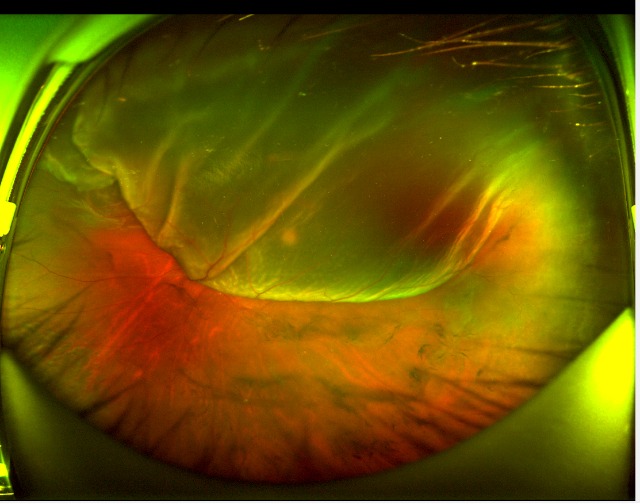

< 본원 응급 당일 망막박리 수술받은 케이스 사진 >

Case 1. 여자 / 67세. 당일 수술 전후 사진

안순열RD1.jpg

안순열RD2.jpg